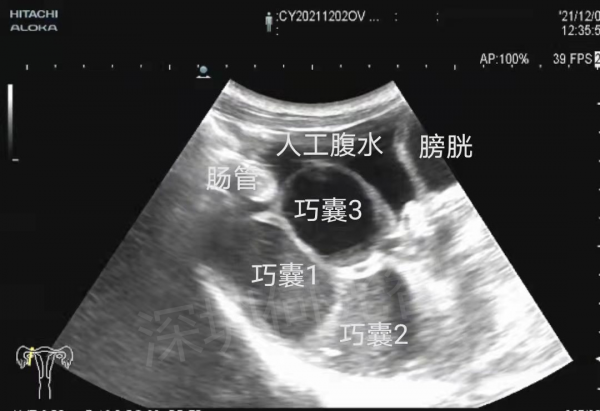

按照預約時間,孟小姐來到了何光智主任所在的介入超聲專家門診。透過詳細詢問病史,查閱過往檢查結果,現場超聲檢查,確認了右側附件區有三個囊腫,其中靠近深部的兩個囊腫(巧囊1與巧囊2),大小分別為55×52×46mm(超聲估測70mL)、36×34×35mm(超聲估測22mL),靠近淺部的一個大小為33×32×27mm(超聲估測14mL),確實需要治療。

鑑於孟小姐未婚未育,超聲介入硬化治療是理想的治療方案,但目前只有經腹穿刺的途徑可供選擇,然而囊腫位於盆腔深處,前方有腸管、子宮及膀胱阻擋,直接穿刺變為不可能。聽到這種情況,孟小姐才知道她的病情治療起來真是困難,之前在網上諮詢的專家並沒有錯,這種情況真的只有腔鏡手術一條路,可孟小姐擔心手術剝離囊腫對卵巢造成損傷,影響以後的生育,這下她又犯了愁。

術前磁共振提示右側附件區多發囊性佔位,考慮巧克力囊腫。囊腫被前方的腸管遮擋,經腹穿刺路徑受阻。

在確認了孟小姐的治療意願後,何光智主任向她提出了一個創新性的方案:將原本用於子宮肌瘤消融的“人工腹水”技術移植到困難巧囊的治療上,方法是向盆腔灌注生理鹽水,把囊腫前方的腸管漂移走,利用人工腹水作為通道,創造出經腹穿刺深部囊腫的安全路徑!目前這種方法已在本院有多例手術案例,皆獲得成功,幫助多名困難巧囊患者成功完成治療。

孟小姐一聽喜出望外,“就按照這種治療方案進行!”按照術前檢查及規劃,何光智主任團隊技術嫻熟地透過穿刺針向盆腔注入生理鹽水,當注入液體達到400ml時,腸管像預計的一樣向上漂移,三個囊腫沒有了阻礙,原形畢露,完全暴露在超聲顯示之下!